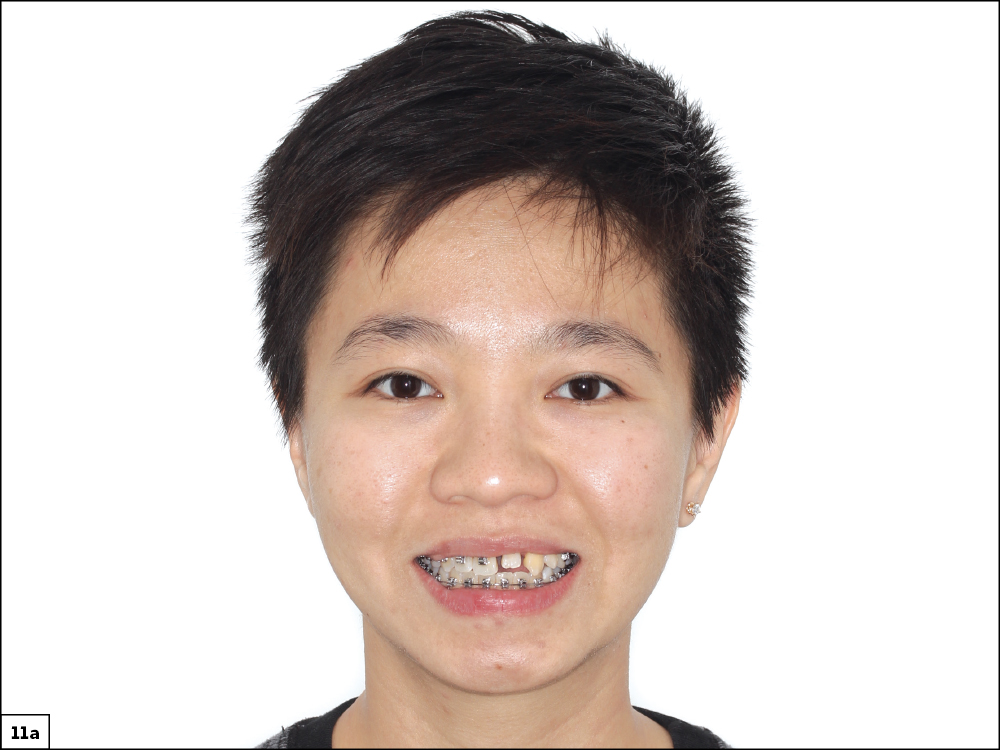

Figures 11a, 11b: A before-and-after comparison of the patient’s smile shows the extensive improvements that took place through our multidisciplinary collaboration. She will enjoy this new look as she moves forward in her life with renewed confidence.